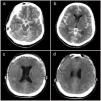

Presentamos el caso de una mujer de 31 años remitida a nuestro departamento con una paraparesia asimétrica progresiva de 10 meses de evolución y disfunción vesical ocasional. Con el diagnóstico de malformación arteriovenosa espinal de tipo IV, se realizó una embolización programada tras la que se produjo una hemorragia subaracnoidea masiva debido a la laceración de la arteria espinal anterior que precisó una craniectomía bifrontal urgente. Discutimos el papel del neurocirujano en el tratamiento de las complicaciones derivadas del tratamiento endovascular de la patología espinal.

We reported a 31 years old female referred to our department with progressive asymmetric spastic paraparesia for 10 months of evolution and occasional bladder dysfunction. With the diagnosis of a type IV arteriovenous malformation, a scheduled embolization was performed resulting in a massive subarachnoid hemorrhage due to the ASA laceration requiring an emergency bifrontal craniectomy. We discuss the neurosurgeońs role in complications during endovascular spinal vascular pathology treatment.